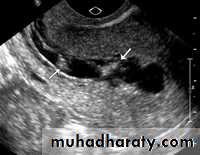

Transvaginal ultrasound may be done to measure the thickness of the endometrium. Thick, it may mean that endometrial hyperplasia is present.The only way to tell for certain that cancer is present is to take a small sample of tissue from the endometrium and study it under microscope.